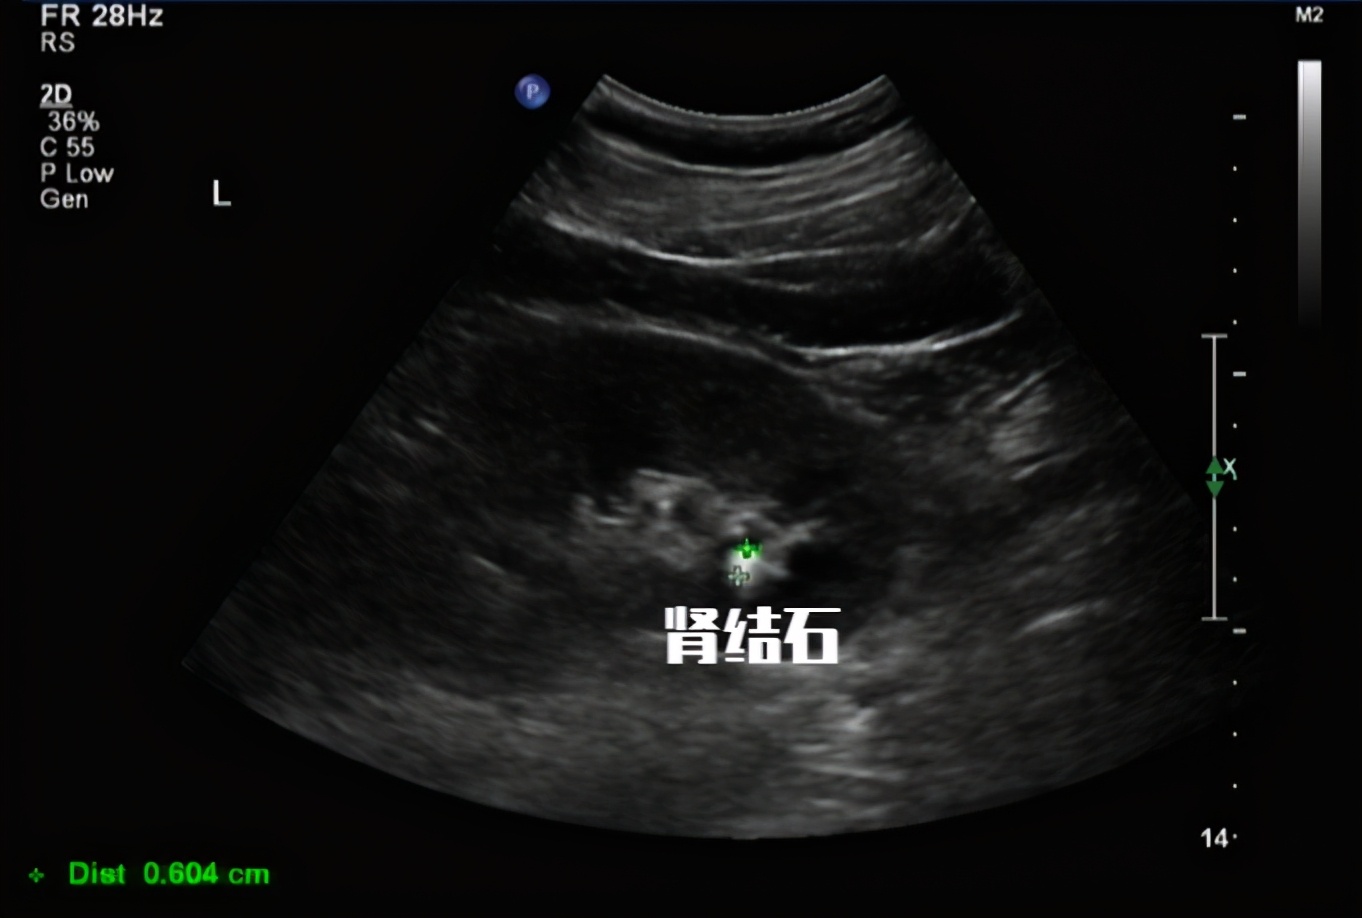

Blood in the urine can be a sign of infection, kidney stones, or cancer, especially bladder cancer. It can be scary to see blood in urine, also called hematuria. Microhematuria, or microscopic traces of blood in the urine, can happen for many reasons, including vigorous exercise or kidney. Healthcare providers label blood in urine as gross, microscopic. What does it mean if your urine occult blood result is too high? In many cases, the cause is harmless. Hematuria is the medical name for the presence of blood cells in urine (pee). In healthy individuals, fewer than 1000 red cells are excreted in the urine per. Occult blood in urine, also referred to as hidden blood in urine,. Anyone with blood in their urine should have a doctor investigate the cause.